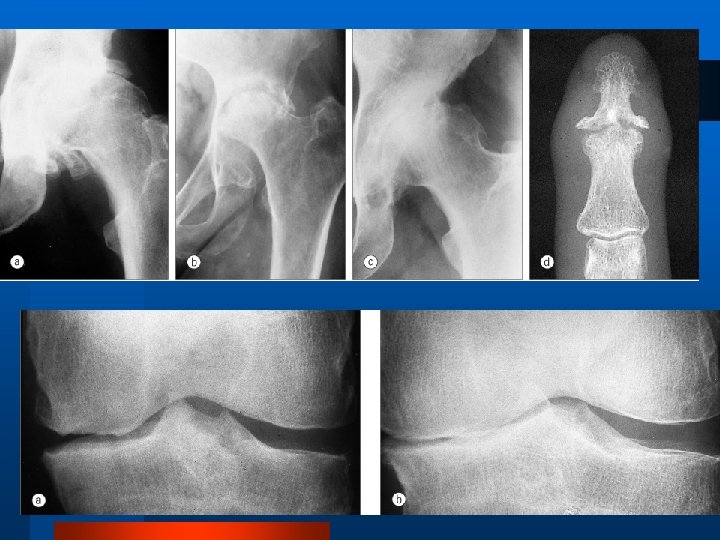

Examenul radiologic l Radiografia simplă este cel mai util mijloc imagistic în artroză, atât pentru diagnostic, cât şi pentru urmărirea evoluţiei. Aspectul l Îngustarea spaţiului articular l Scleroză subcondrală l Osteofitoză marginală l Pseudochisturi sau geode

Gradarea Kellgren-Lawrence 0: Normal I: Osteofite posibile şi posibil pensarea spaţiului articular II: Osteofite definite şi posibil pensarea spaţiului articular III: Osteofite moderate multiple, pensarea definită a spaţiului articular, scleroză şi posibil deformare a conturului osos IV: Osteofite mari, pensarea marcată a spaţiului articular, scleroză severă, şi deformare definită a conturului osos

Criterii de Diagnostic Coxartroza (artroza şoldului) Dureri în şold în majoritatea zilelor pe parcursul lunii precedente 2. Existenţa osteofitelor în şold şi/sau în acetabulus 3. VSH ≤ 20 mm/oră 4. Limitarea rotaţiei interne a şoldului 1. Diagnosticul OAD se stabileşte în baza existenţei punctelor 1 şi 2 sau punctelor 1, 3 şi 4. Sensibilitate 91 %, specificitate 89 %.